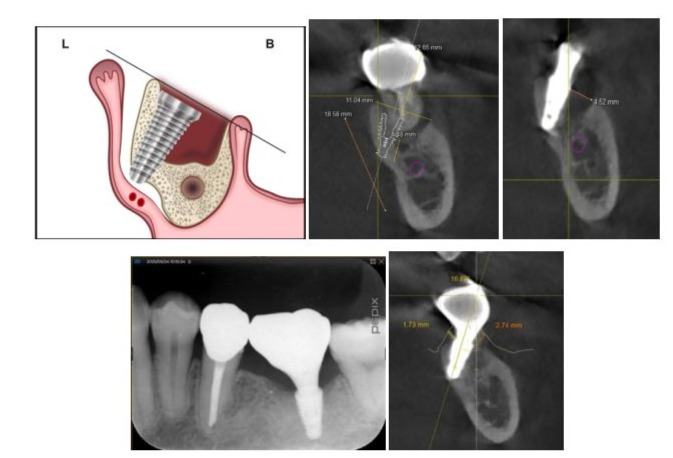

However, if insertion of the implant under that condition is not possible, the authors use tilted implants anchored to the lingual cortical plate of bone in the lower jaw and between the palatal cortical and lateral walls of the maxillary antrum cortical bone, avoiding maxillary sinus penetration (Figures 4a and 5a). One of the major concerns with the tilted implant procedure in the mandibular molar region can be perforation of the lingual cortical bone, possibly leading to serious hemorrhage [24,25]. Two important things must be done to prevent these complications. The first is precise preoperative diagnosis using CBCT with virtual implant simulation. The location of the implant platform is decided from the inferior alveolar nerve, both buccal and lingual bone crests, and the opposite tooth. Implant tilting, width, and length are also simulated based on the perforation point to the lingual cortical plate of bone at the same time (Figure 4b). The second is sufficient mucoperiosteal flap elevation in the surgery (Figure 4a). Elevation far beyond the expected perforation point is recommended for placing a mucosal dissector or saline-soaked gauze for soft tissue protection against the apex of preparation drills (Figure 4a). If these two things are appropriately done, it is the authors’ view that complications will never occur. The major advantage of this method is that it can achieve reliable initial stability with high ITV (more than 40 Ncm) [27,28]. When placing implants to cortical plate of bone with increased ITV of more than 40 Ncm, decreased or absent micromotion might help achieve predictable osseointegration [28]. This can lead to complete early final restoration, and, ultimately, the treatment period is shortened [28,29]. It has been reported that a definitive screw-retained prosthesis with zirconia was placed on standard and zygomatic implants for an edentulous maxilla seven days postoperatively [31]. Soft tissue of post-surgical healing around an implant appears to be completed after 2 weeks, and structural integrity is complete at the same time (about 2-3 weeks). Maturation of barrier function requires 6-8 weeks of healing [32]. This is based on the authors’ hypothesis that the goal is to improve barrier function by providing a highly biocompatible final prosthesis early on (2-3 weeks) and avoiding the need to attach and remove the implant abutments during soft tissue barrier maturation of 6-8 weeks post-surgically. After tooth extraction and immediate implant placement, the bone undergoes significant modeling in the edentulous ridge of the alveolar process, resulting in a decrease of the ridge dimension [19]. Moreover, when a flap procedure has been added, bone modeling might be accelerated. Regarding to the space distance between an implant and the adjustment bone wall, if the space is >2 mm, the site ought to be grafted with primary closure. In contrast, even if the space is >2 mm, success of the implant may be attained with no primary closure, no grafting, and no flap elevation [4]. In type D and E sockets, flap elevation might be required; thus, aggressive SPT is recommended if the gap is ≥3

mm [15,15,33,34]. Moreover, the implant platform can be located 0.5-1.0 mm below the line connecting the crest of buccal bone and the crest of lingual bone (Figure 4a,b) [34]. In many cases, the height of the crest of buccal bone is located below the crest of lingual bone, and the line tilts buccally, so that the implant will be also tilted buccally (Figure 4a-e). Fixation to the lingual cortical plate of bone may be required.

Figures 4a to 4e: a. A schema of a type E socket: L, Lingual and B, Buccal. Please pay attention to the position of the implant platform; b. A treatment plan with coronal sectional image for a case of healthy 51-year-old male patient company employee who visited for tooth pain. A type E socket without any septal and root sockets. Furthermore, there might be a lack of axial bone required for initial stability; c. Existing gap of about 5 mm; d. A periapical radiograph after 3 years; e. Soft tissue thickness of about 3 mm observed on the new bone into the gap.

Figures. 5a to 5e: a. A Schema of a type E socket: P: Palatal and B: Buccal;b. A treatment plan with coronal sectional image for a case of healthy 73-year-old female patient occupied housewife who visited for tooth pain for an implant placement in the type E socket; c. The implant with a 26.7-degree angle to the occlusal plane with sectional image 3 years after the surgery; d. Buccal view at the time of restoration with soft tissue placed 2 weeks after the surgery; e. Buccal view of the restoration with soft tissue 12 weeks after the surgery.

Treatment of a Type E Socket in the Maxilla: Case 7.

The tilted implant in a type E socket in the maxilla might have a higher ITV than an axial implant. The reason is that, whereas axial implants rely on the cortical bone plate of the maxillary sinus floor alone for stability, a tilted implant can be inserted into the region surrounded by two or three walls: the lateral cortical bone of the maxillary sinus floor, the cortical bone plate of the palate, and sometimes the cortical plate of bone on the nasal cavity floor (Figure. 5a-c). Therefore, a longer implant and higher ITV than an axial implant can be expected, if anatomical conditions permit. Under these circumstances, minimal flap or flapless elevation under good visibility would be possible. The soft tissue depression created at the time of surgery appears to gradually return to a normal shape over a period of approximately 6 to 12 months as bone forms in the gap area (Figure 5d,e).